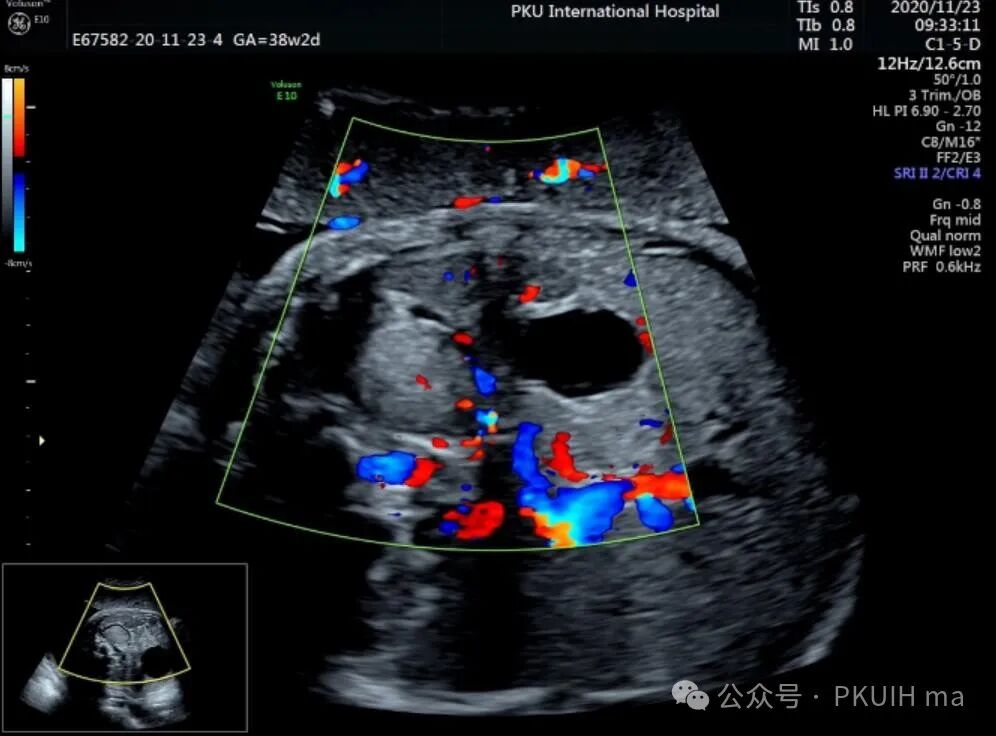

上图是一例在孕晚期发现的肾上腺占位,生后病理证实为神经母细胞瘤的患儿,生后及时做了治疗预后非常好,目前宝宝各项指标都很好。

同时在孕晚期也发现孕妇羊水增多

这几年我们在孕晚期发现有3例神经母细胞瘤胎儿,预后都很好。在孕晚期超声中建议常规扫查下胎儿双肾区